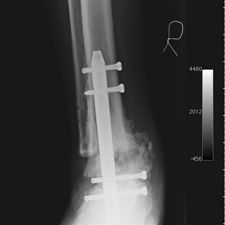

Because of his diabetic and vascular condition, one of the options given to him was amputation. He is a motivational speaker and it would have seriously affected his functioning. He sought our advice and he was told that the option of amputation was viable but we would recommend an arthrodesis of the ankle using an intra-medullary device (BIOMET -http://www.biomet.com/regions/caribbean/trinidadAndTobago.cfm) which we have previously utilized to good effect in cases like these.

He opted to have a right hind foot arthrodesis, which was carried out utilizing an intramedullary arthrodesis nail, which was performed in July 2011.

He has gone onto have good healing and fusion of the ankle with preservation of his foot and has allowed him to mobilize independently without pain and return to his job. At last review he was independently mobilizing and did not have any pain, He has restarted working and has no problems.